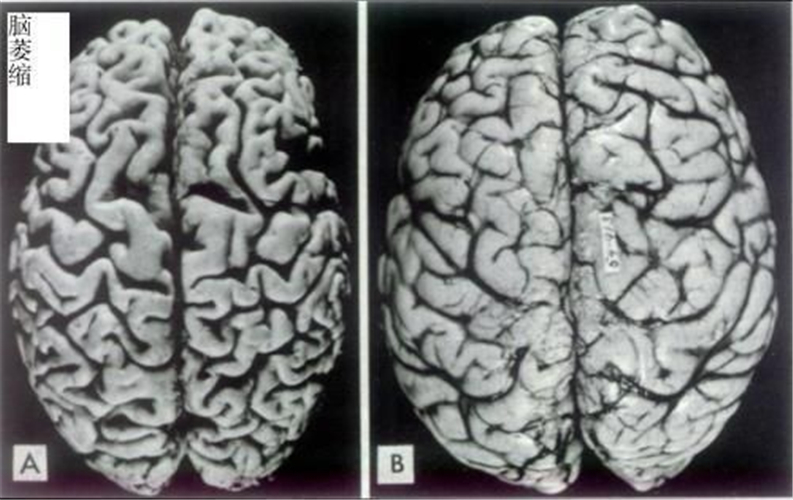

腦萎縮圖片

先天性腦萎縮與正常大腦對比